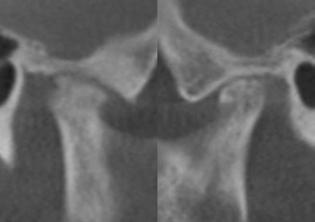

Figure 1 (left): A photo of a 69-year-old woman with a 2 mm anterior open bite and an excessive interlabial gap of 9 mm. Figure 2 (right): The sagittal slices of the above patient’s mandibular condyles reveal discontinuity of the cortical outline at the fossa and condyle (erosions). The altered condyles are flat along their path of function when she pushes her lower jaw forward to get the lips to touch in speaking, chewing, and breathing through her nose. Image captured using Dolphin® software (www.dolphinimaging.com)

Figure 3 (left): This same 69-year-old has undergone orthognathic surgery (bilateral sagittal split osteotomies and genioplasty) to close her open bite and shorten her anterior face height. This allows her lips to touch at rest and reduces energy usage to breathe, eat, and communicate. Figure 4 (right): The energy reduction at the mandibular condyles allows them to heal as evidenced by the recortication of the bone with the disappearance of the bony erosions. Image captured using Dolphin software (www.dolphinimaging.com)